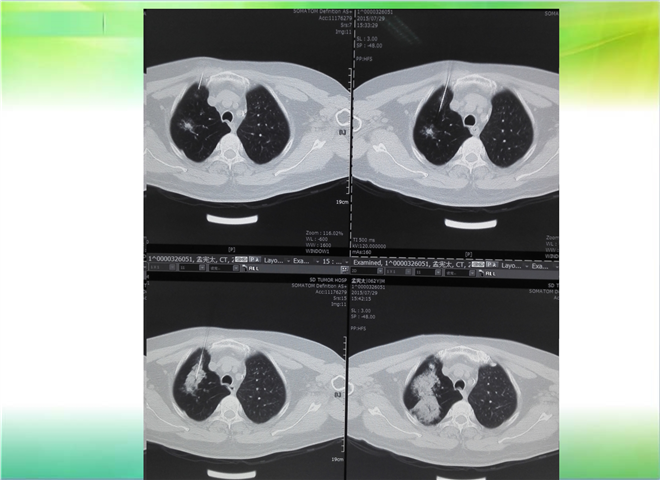

CT引导下穿刺活检术